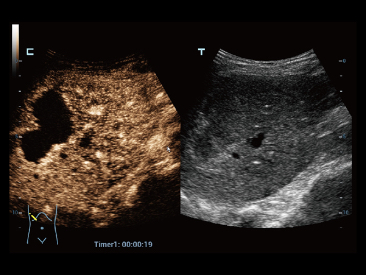

UWN+?(–љ–µ–ї–Є–љ–µ–є–љ–∞—П –≤–Є–Ј—Г–∞–ї–Є–Ј–∞—Ж–Є—П –≤ —Г–ї—М—В—А–∞—И–Є—А–Њ–Ї–Њ–Љ –і–Є–∞–њ–∞–Ј–Њ–љ–µ) –і–ї—П –Ї–Њ–љ—В—А–∞—Б—В–љ–Њ–є —Н—Е–Њ–≥—А–∞—Д–Є–Є –њ–Њ–Ј–≤–Њ–ї—П–µ—В —Б–Є—Б—В–µ–Љ–µ Resona 6 –Њ–±–љ–∞—А—Г–ґ–Є–≤–∞—В—М –Є –Є—Б–њ–Њ–ї—М–Ј–Њ–≤–∞—В—М –Ї–∞–Ї –≤—В–Њ—А—Л–µ –≥–∞—А–Љ–Њ–љ–Є–Ї–Є, —В–∞–Ї –Є –љ–µ–ї–Є–љ–µ–є–љ—Л–µ –њ–µ—А–≤–Є—З–љ—Л–µ —Б–Є–≥–љ–∞–ї—Л. –Ґ–µ—Е–љ–Њ–ї–Њ–≥–Є—П –њ–Њ–Ј–≤–Њ–ї—П–µ—В —Б–Њ–Ј–і–∞–≤–∞—В—М –Є–Ј–Њ–±—А–∞–ґ–µ–љ–Є—П –Ї–Њ–љ—В—А–∞—Б—В–љ–Њ–є —Н—Е–Њ–≥—А–∞—Д–Є–Є –±–Њ–ї–µ–µ –≤—Л—Б–Њ–Ї–Њ–≥–Њ –Ї–∞—З–µ—Б—В–≤–∞ —Б –±–Њ–ї—М—И–µ–є —З—Г–≤—Б—В–≤–Є—В–µ–ї—М–љ–Њ—Б—В—М—О –Ї–Њ –≤—В–Њ—А–Њ—Б—В–µ–њ–µ–љ–љ—Л–Љ —Б–Є–≥–љ–∞–ї–∞–Љ, –±–Њ–ї—М—И–Є–Љ –≤—А–µ–Љ–µ–љ–µ–Љ –і–µ–є—Б—В–≤–Є—П –∞–Ї—В–Є–≤–љ–Њ–≥–Њ –≤–µ—Й–µ—Б—В–≤–∞ –Є –±–Њ–ї–µ–µ –љ–Є–Ј–Ї–Є–Љ–Є —В—А–µ–±–Њ–≤–∞–љ–Є—П–Љ–Є –Ї –Є–љ—В–µ—А–≤–∞–ї—Г –Є–Ј–Љ–µ—А–µ–љ–Є—П.